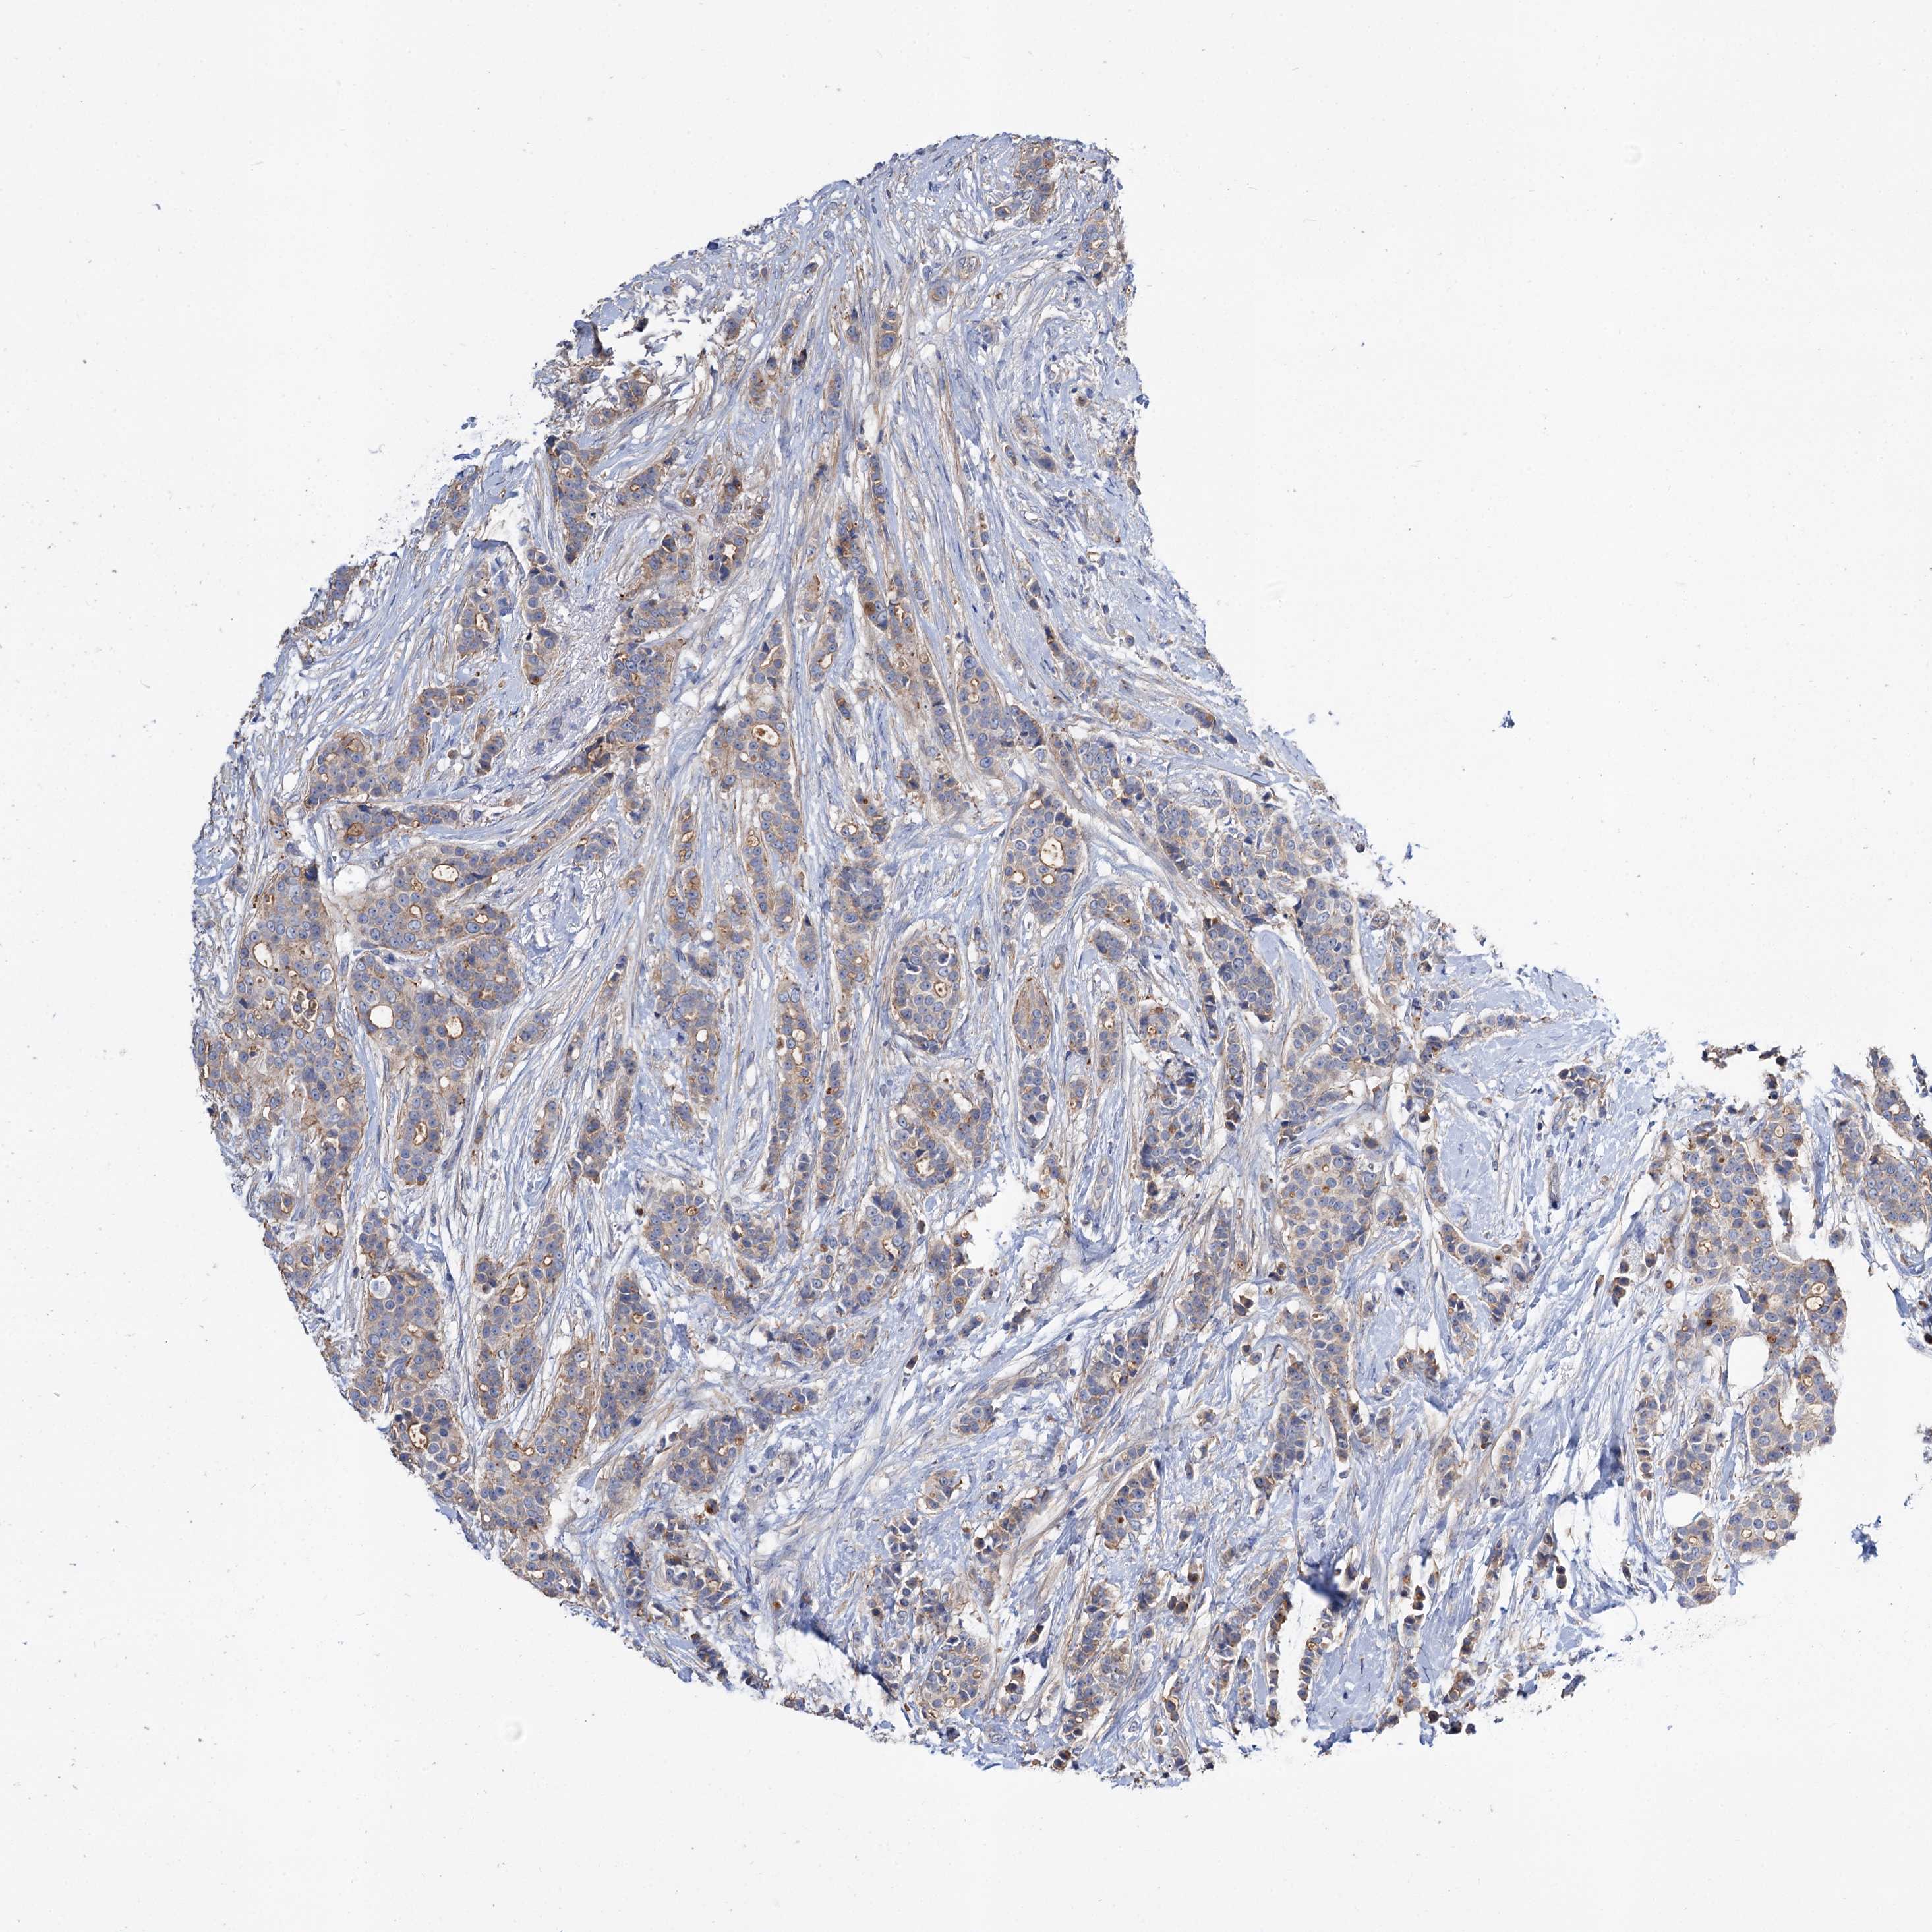

CANCER BREAST CANCER Show tissue menu

BRCA TCGA BRCA VALIDATION PROTEIN EXPRESSION